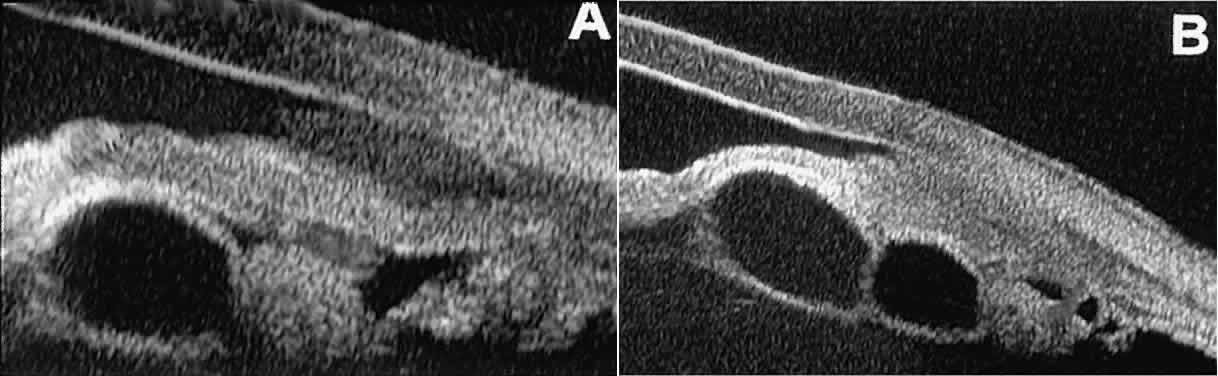

Stratified squamous epithelial cysts (Fig. 23) are almost exclusively unilateral and unifocal,15 have substantially thicker walls than do primary neuroepithelial cysts, and usually contain prominent intracavitary particles (desquamated epithelial cells). Almost all such cysts involve the peripheral iris and angle region. Such cysts are usually secondary to prior ocular surgery or laceration in which conjunctival epithelial cells were implanted into the iris stroma.

Fig. 23. UBM features of stratified squamous epithelial cysts of iris. A. Thick-walled implantation cyst of stratified squamous epithelium replacing normal iris. Note intracavitary particles. B. Bilobed stratified squamous epithelial inclusion cyst of iris with prominent intracavitary particles.

Secondary neuroepithelial cysts occur rather frequently in association with solid tumors of the iris or ciliary body.15 On UBM (Fig. 24), such cysts appear quite similar to the primary neuroepithelial cysts described above; however, they are associated with a solid mass arising within the iris or ciliary body.

Fig. 24. UBM appearance of neuroepithelial cysts associated with solid tumors of the iris and ciliary body. A. Single neuroepithelial cyst associated with iris melanoma. B. Multiple neuroepithelial cysts associated with iridociliary melanoma.

Intratumoral cavitation is a relatively uncommon cystic feature of some solid tumors. An intratumoral cavity appears on UBM as a well-defined sonolucent space within the stroma of the solid tumor (Fig. 25).15 The lack of pulsation during the UBM examination of such lesions and the diameter of the cavity enable the clinician to differentiate the cavitation from a large blood vessel.

Fig. 25. Cavitation within iridociliary melanoma revealed by UBM. The cavity is entirely sonolucent, and the tumor tissue adjacent to the cavity appears similar in reflectivity to that in other areas of the tumor.